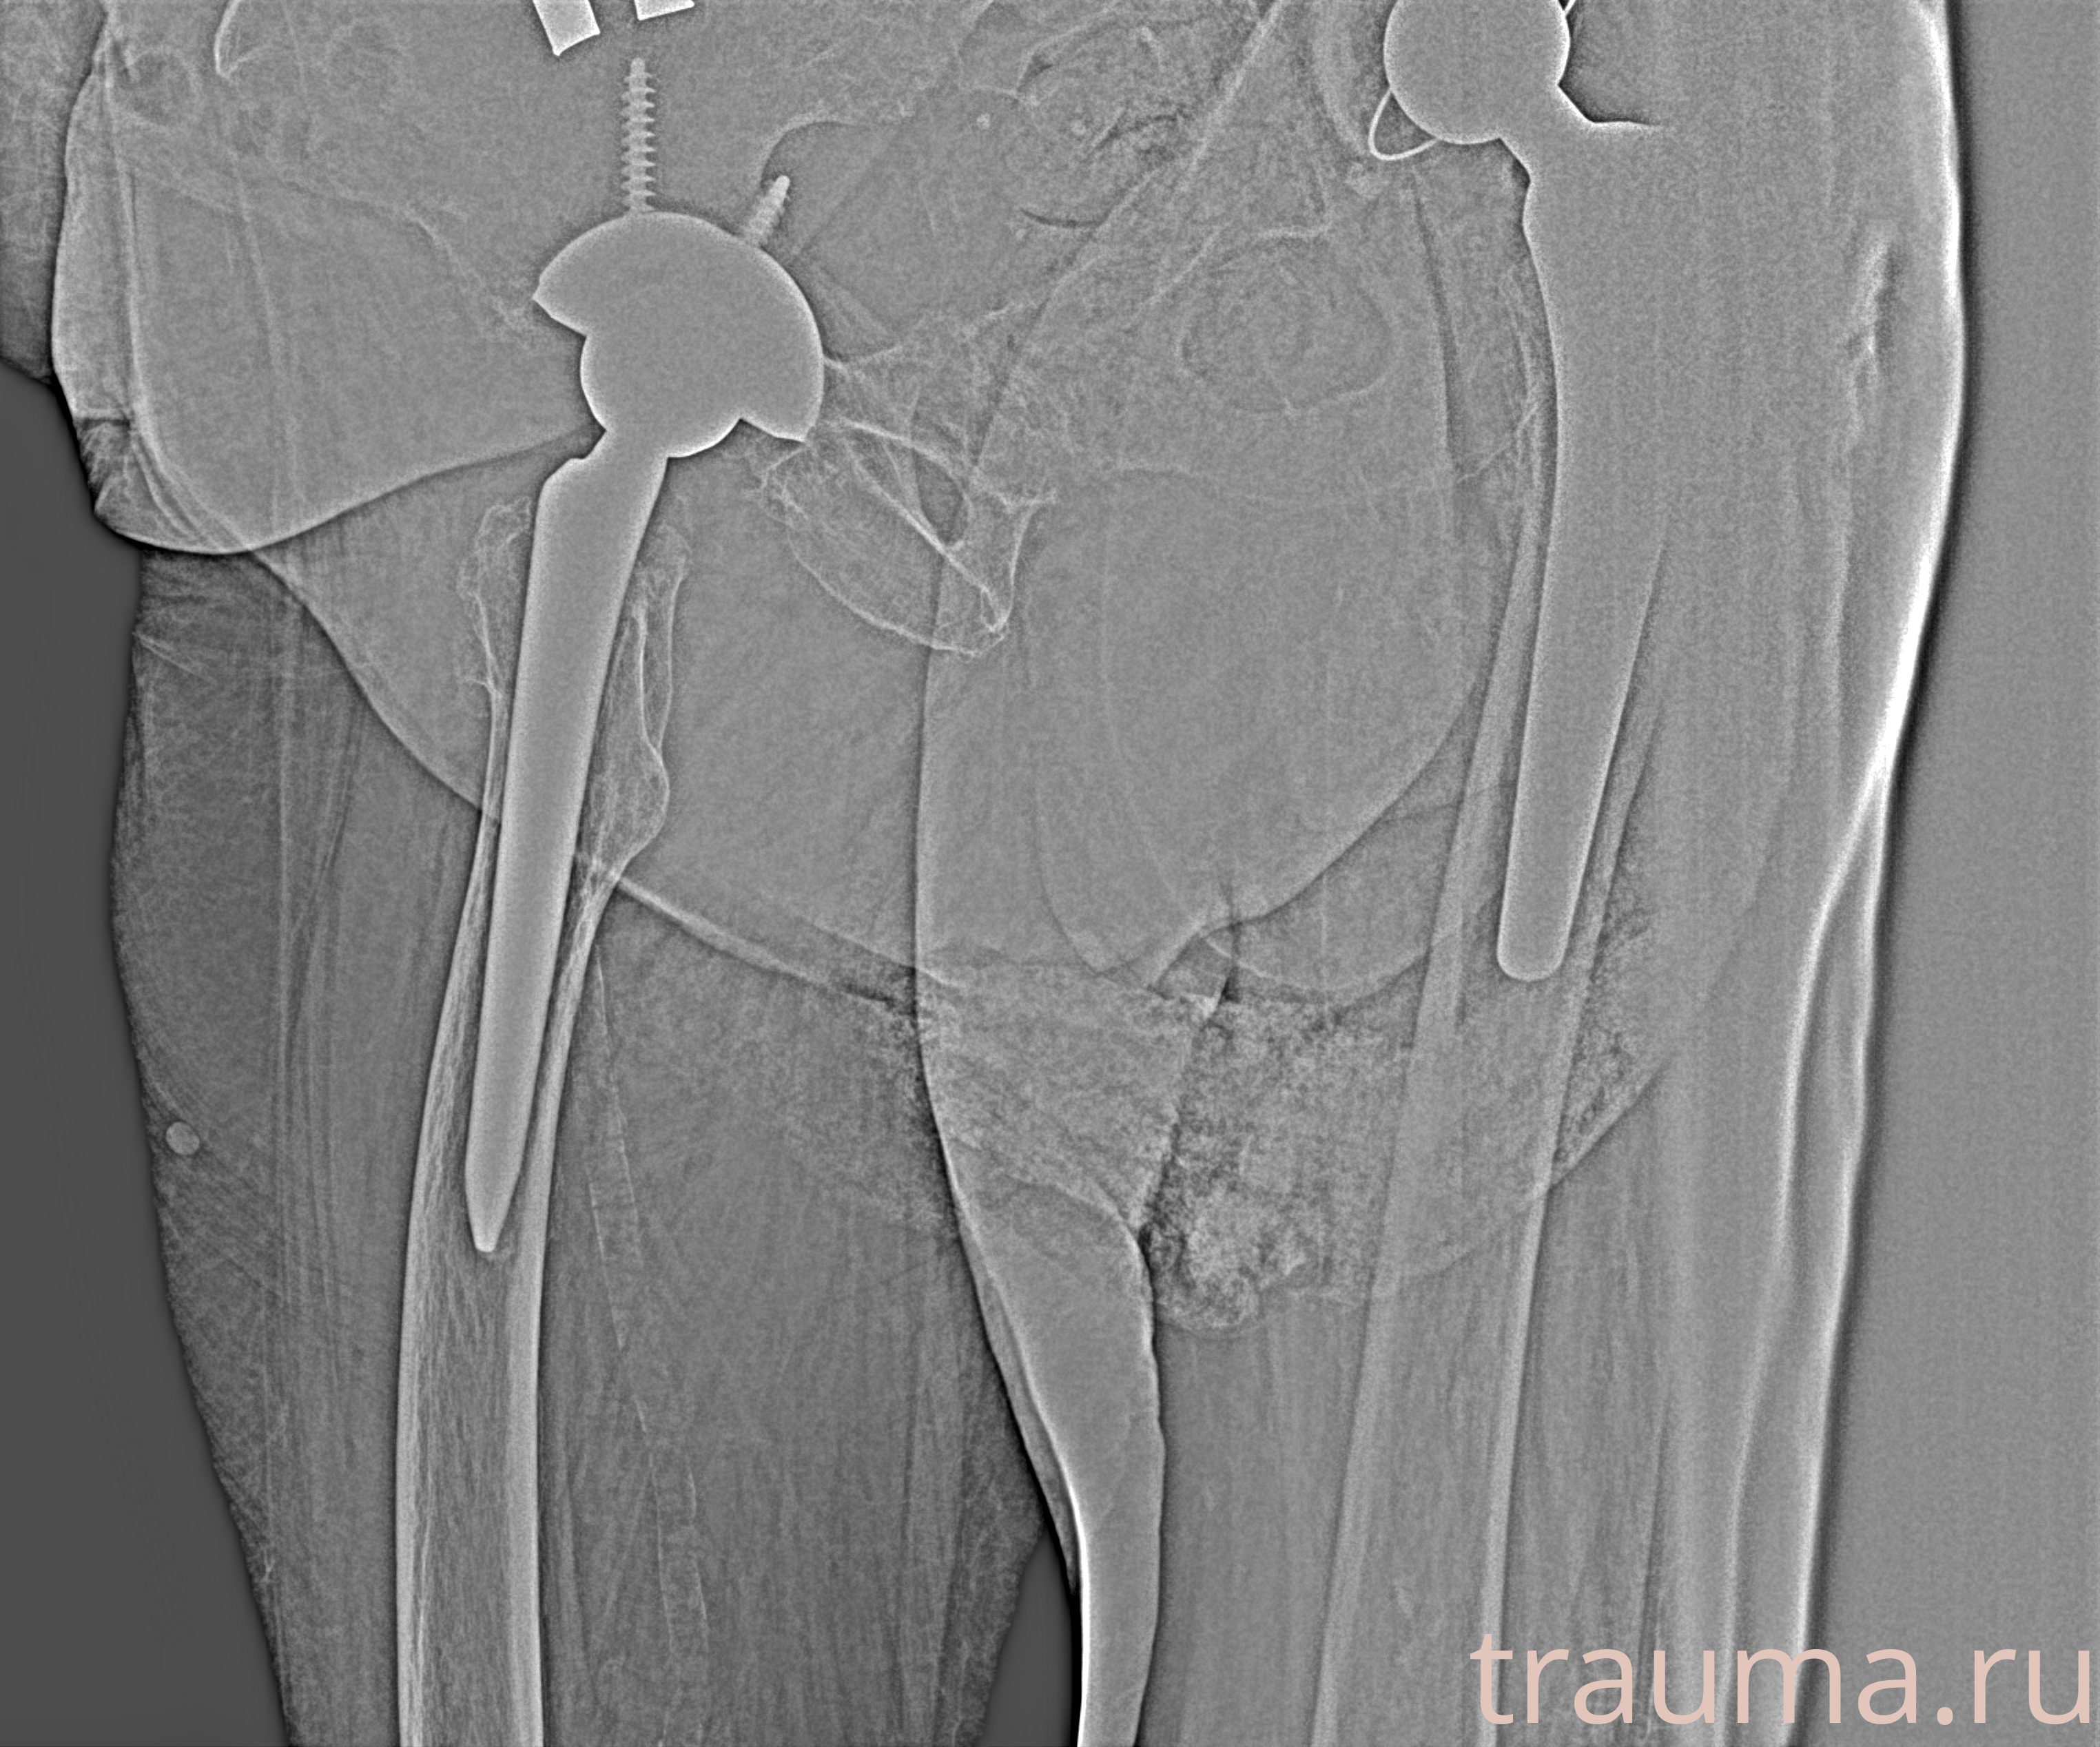

Рентгенограммы

Рентген на дому: по вашему адресу приезжает врач-рентгенолог, травматолог-ортопед с мобильным рентгеновским аппаратом, проводит диагностику травмы или заболевания, делает необходимые рентгенограммы, дает рекомендации по дальнейшему лечению. Получить качественные снимки в домашних условиях возможно благодаря уникальной методике, разработанной МосРентген Центром для института  Склифосовского